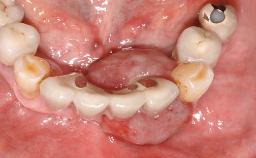

Surgical treatment of a 68-year-old female patient with a distal extension situation in the left mandible. As the CBCT analysis reveals, the bone crest anatomy in the area is not ideal and necessitates an augmentation procedure to achieve a good long-term prognosis for the planned implants and their prostheses.

After the placement of three diameter-reduced two-piece implants the bone is augmented with autologous bone chips and DBBM particles to enlarge the crest volume. The surgery is completed with the application of two membrane layers and primary wound closure.

The case concludes with the presentation of the final prostheses at the 3-year follow-up, demonstrating a stable and pleasing soft- and hard-tissue situation.